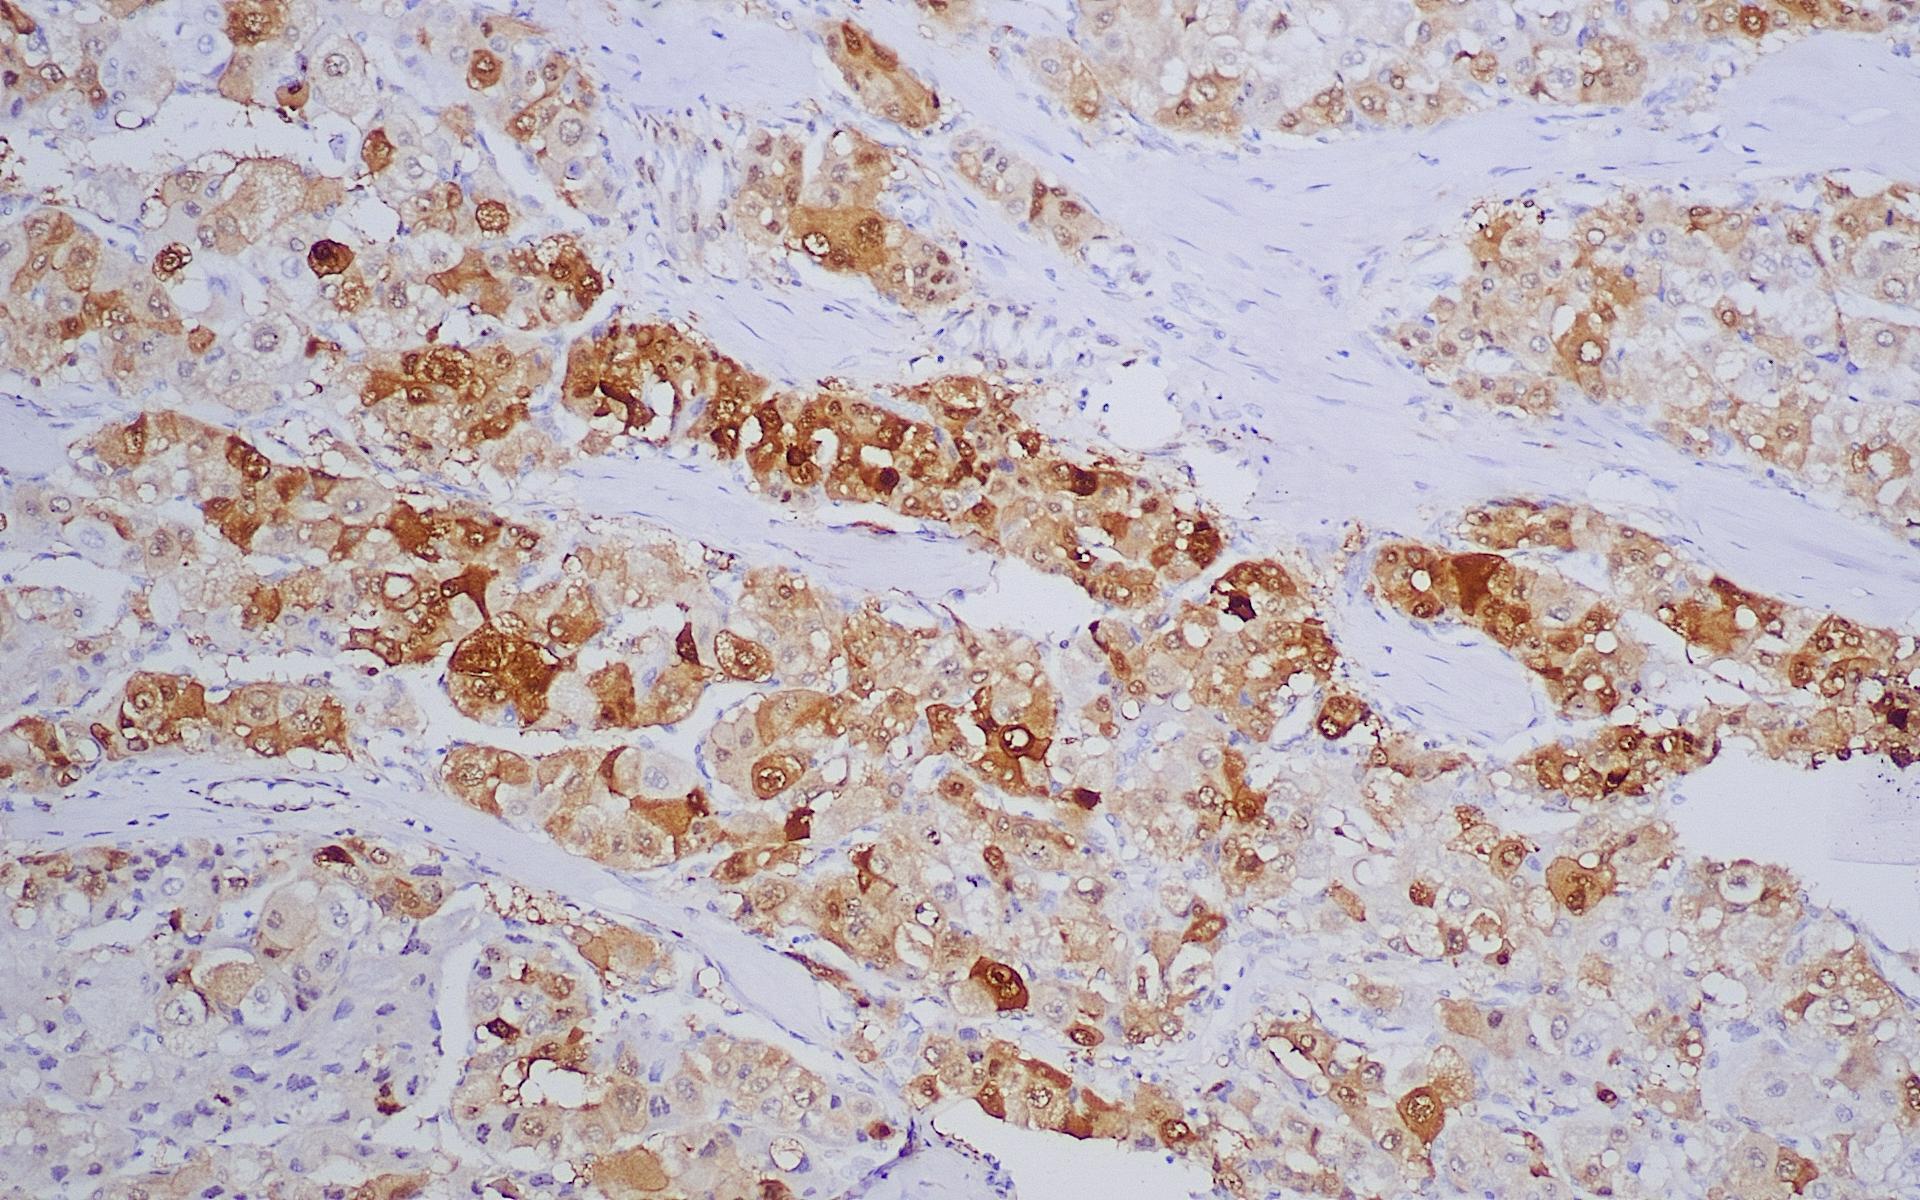

• 染色定位 : 细胞质/细胞核

• 阳性对照 : 肝细胞肝癌

热休克蛋白(Heat Shock Protein)是细胞受应激原刺激后诱导产生的一组应激蛋白,按其分子量不同可分为3种,每组HSPs的分布及功能有所不同。机体细胞在热休克或受到其它外来刺激时诱导HSP的产生,在许多肿瘤中呈高表达,与肿瘤的发生、增殖与分化有关。HSP70在肿瘤中的过表达意味着预后不良及耐药,并常与GPC3和GS联合用于肝细胞癌的研究。

• HSP70肝癌